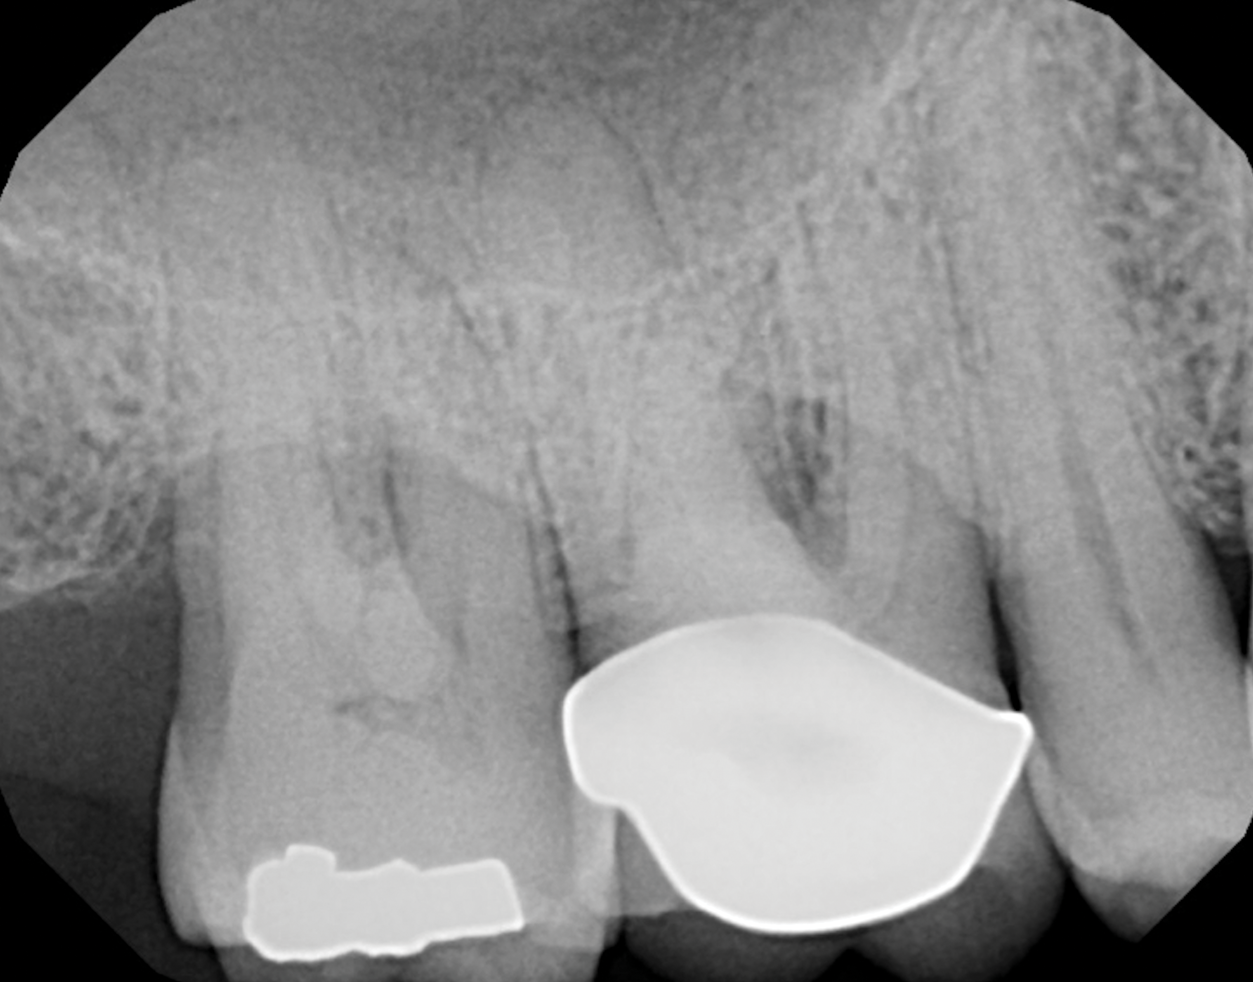

Periodontal examination revealed generalized BOP and PDs up to 9 mm in the maxillary and mandibular molars with multiple furcations in each molar (Figure 2 through Figure 7). He presented with class I mobility in many posterior teeth and class II mobility in teeth Nos. 3 and 9 (maxillary right first molar and maxillary left central incisor, respectively). The periodontist decided to score tooth No. 3 for the PRS, as this was the most periodontally involved molar that was planned to be treated and maintained (Figure 2 and Figure 8). This tooth (maxillary right first molar = score 1) presented with probing depths of 7 mm (score 1); three total furcation invasions (score 3) (mesial [degree II furcation], buccal [degree I furcation], and distal [degree II furcation]); and a class II mobility (score 2). The total PRS for tooth No. 3 was 8, representing a "guarded" prognosis. Based on this score, the likelihood of not losing any teeth to periodontal disease for 15 years was 81%, and for 30 years the likelihood was just 56% (Figure 9).7

Fig 8. Periapical radiograph of the maxillary right first molar (identified as the most periodontally involved molar that was planned to be maintained).

Figure 8

During follow-up periodontal maintenance appointments over time, the patient's PRS for tooth No. 3 was reduced to a score of 5, a "good" prognosis with a 93% chance of periodontally preserving his teeth after 15 years and an 80% chance of doing so after 30 years (Figure 9). The furcation involvement score was reduced with the buccal furcation of tooth No. 3 non-probable (score = 1). The tooth mobility score of No. 3 was reduced by 1 (score = 1). The patient remained in periodontal maintenance every 3 months until 2018 with excellent compliance.17 Review of his PRS at each visit reinforced the positive results of treatment and the importance of his compliance to the "keys to success." His PRS for tooth No. 3 remained stable (score 5).